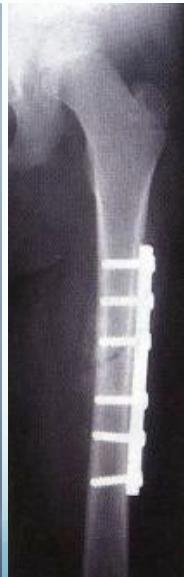

Plating

- For overweight children

- Problems:

- Large scars

- Needs removal